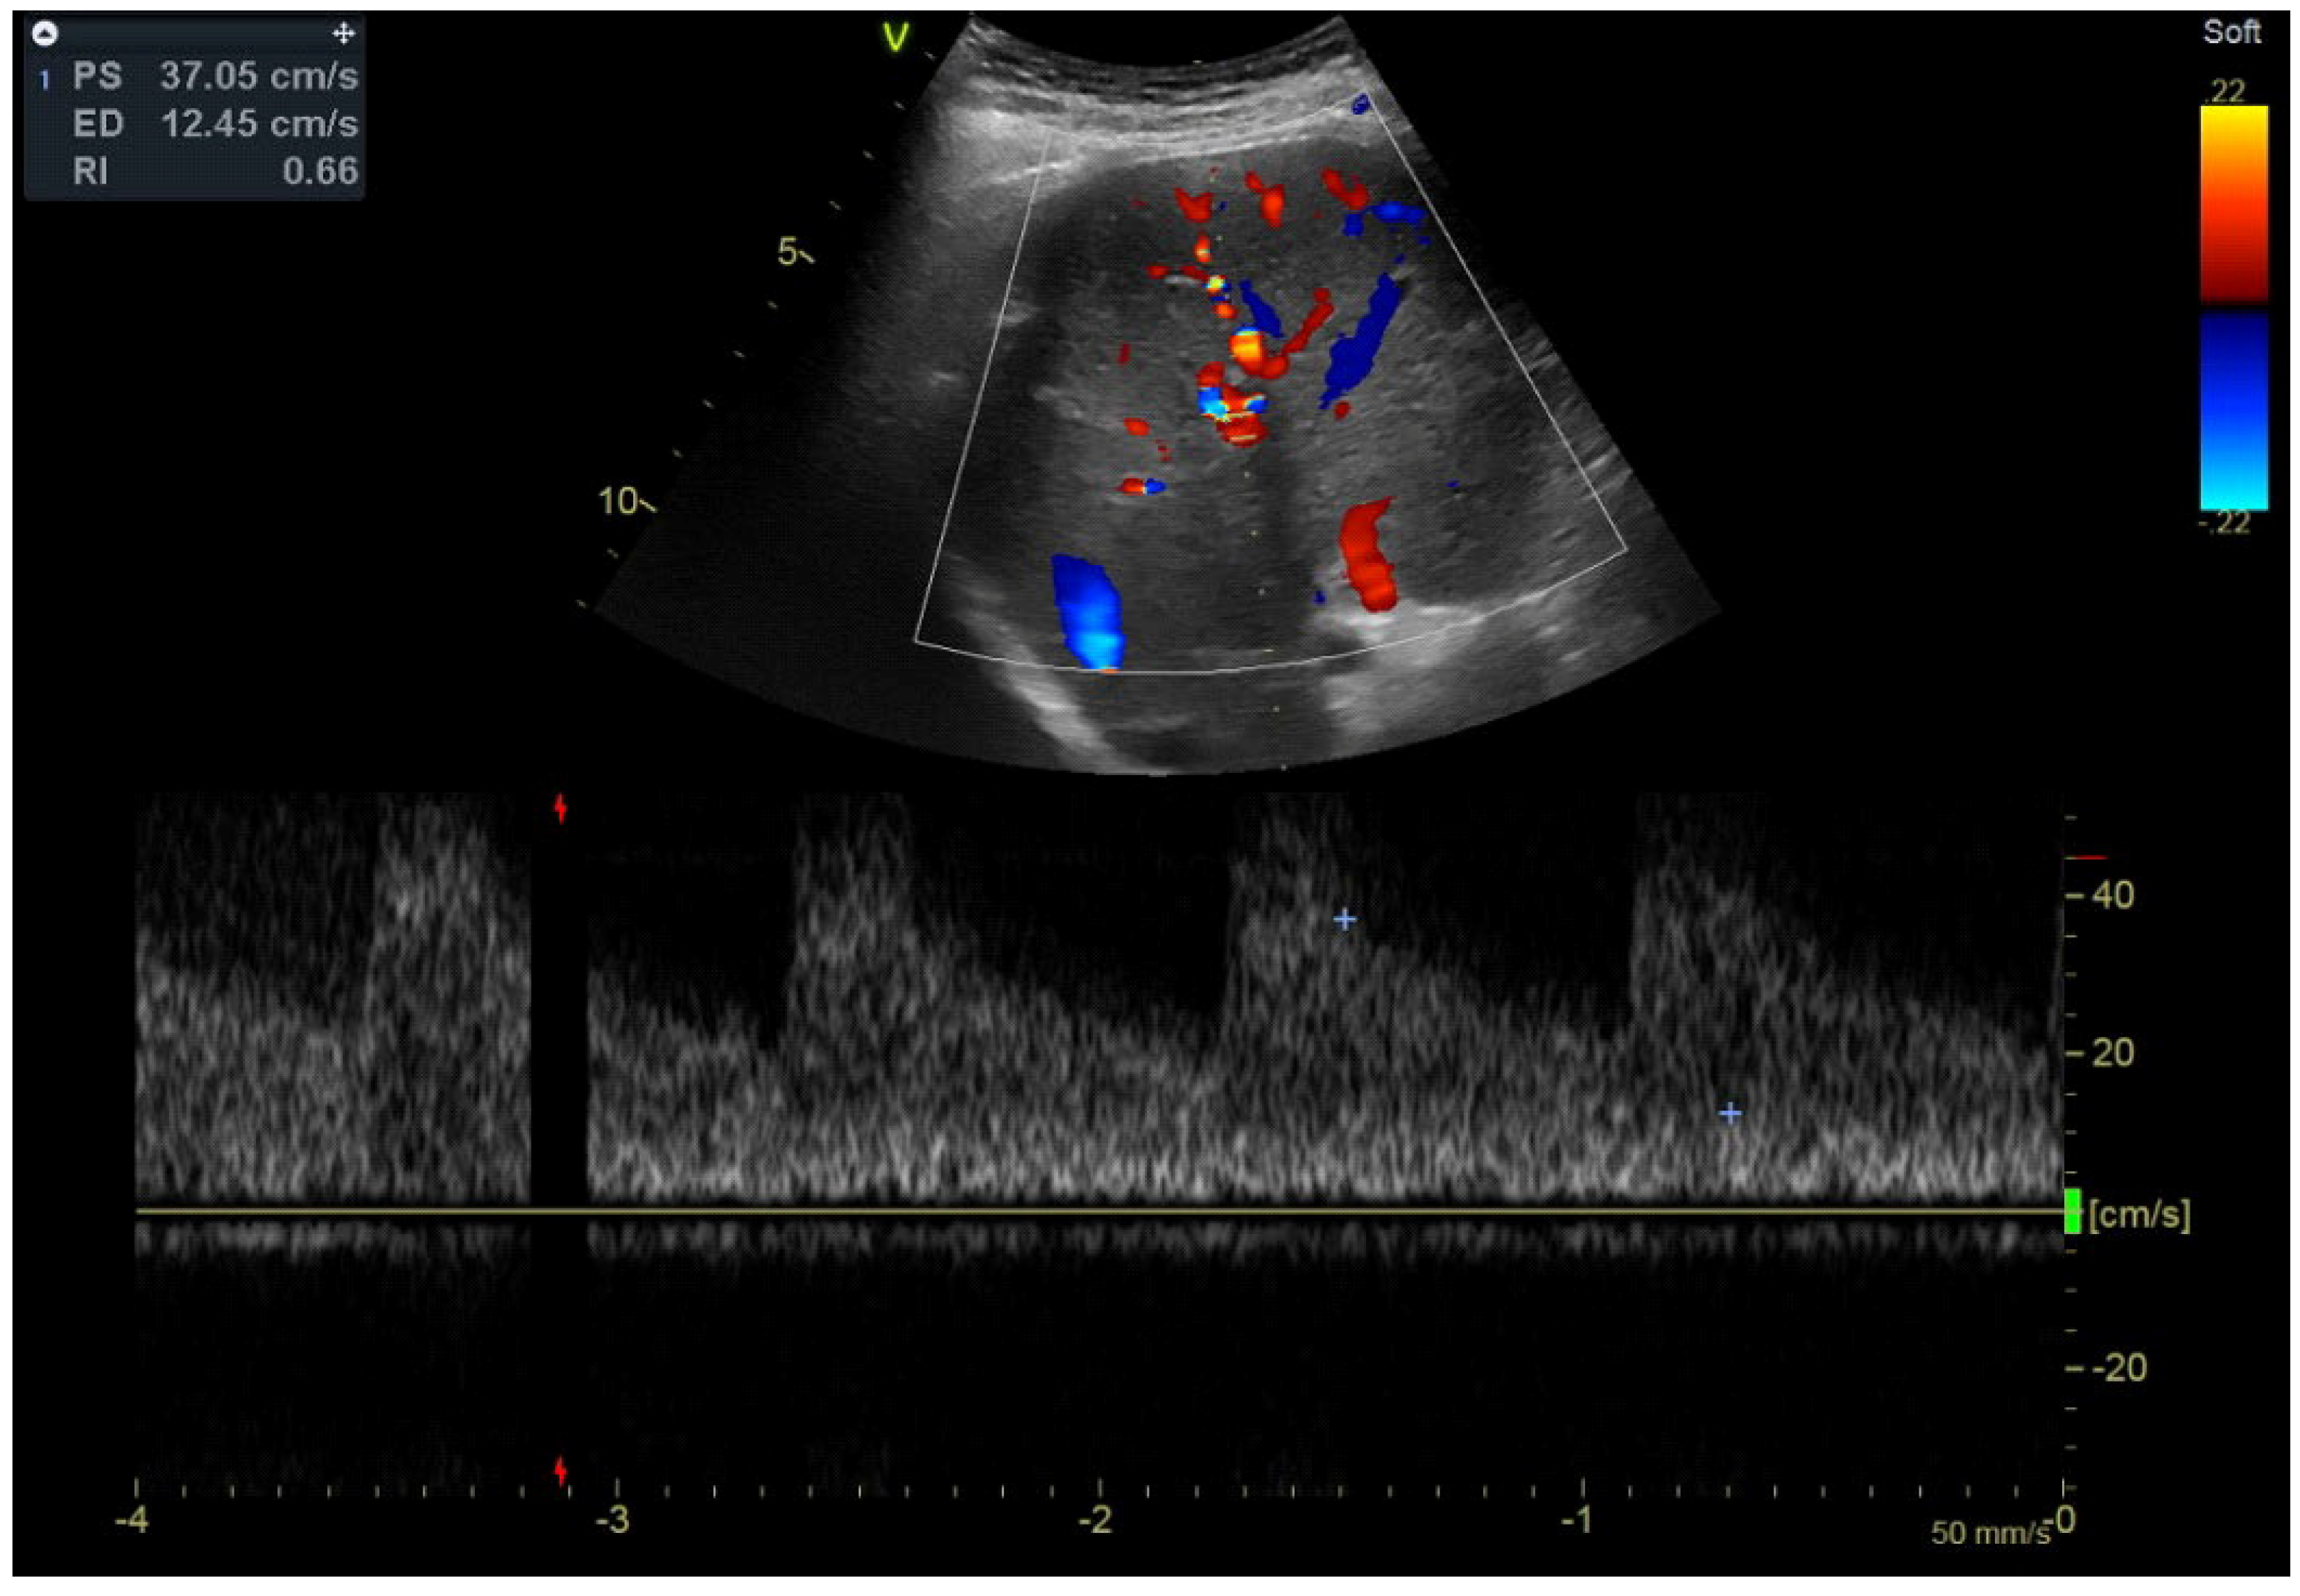

2.2. Imaging Methods